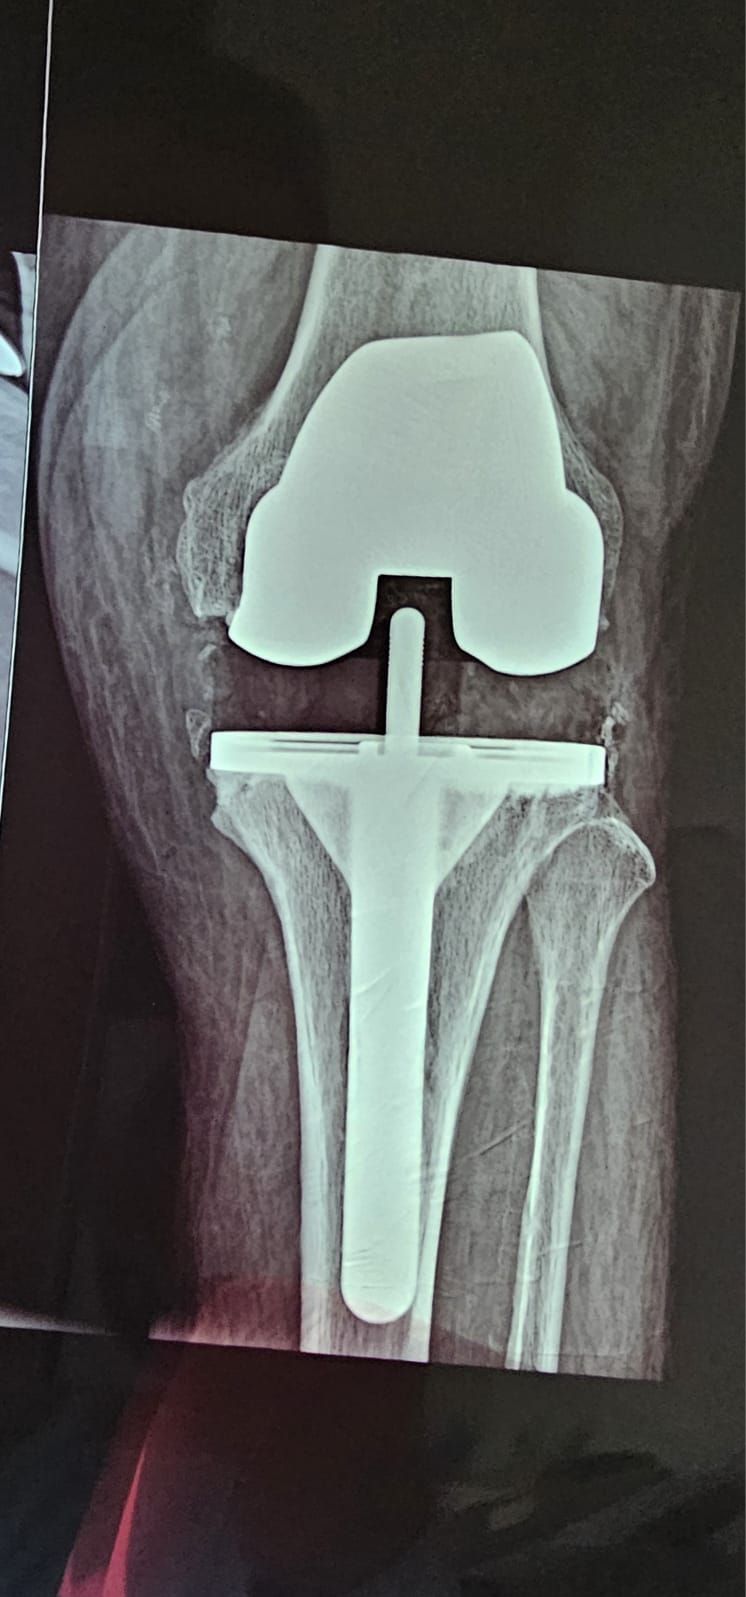

Mi preparación me permite ayudar a mis pacientes en el diagnóstico y tratamiento de lesiones deportivas y problemas articulares, tales como lesiones de ligamentos de rodilla, desgarros de menisco, lesiones del manguito rotador, pinzamiento subacromial, hombro congelado y tendinitis, así como prótesis de hombro y rodilla, brindando siempre una atención personalizada, moderna y enfocada en recuperar tu movilidad y calidad de vida

• Prótesis de Rodilla

Me ayudó muchísimo su atención y calidad humana. Sin duda ortopedista de confianza para mi problema de protesis de rodilla, además que nos explicó detalladamente el problema y el tratamiento. Ya pude caminar nuevamente sin dolor. GRACIAS DR